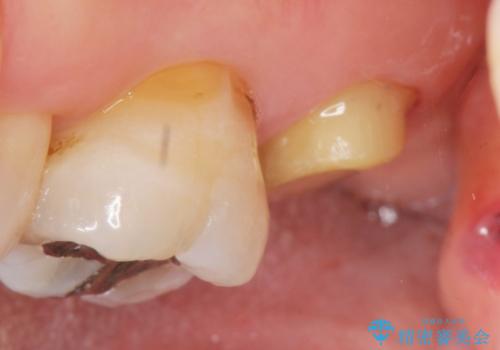

- 根管治療ののち、そのままになっていた歯のクラウン製作を希望され来院されました。

クラウンの将来的な虫歯の再発を防ぐために周囲の歯ぐきを切除することで歯の高さを出し安定した歯周環境にしたのち噛み心地の良いゴールドクラウンを製作します。

クラウンを装着した歯の虫歯の再発を防ぎ長い予後を期待するために削った箇所をしっかりとかぶせる適合の良さが必要はもちろんですが、セメントの漏洩を防ぐためにクラウンの十分な支台高径を歯周外科を行い獲得しました。